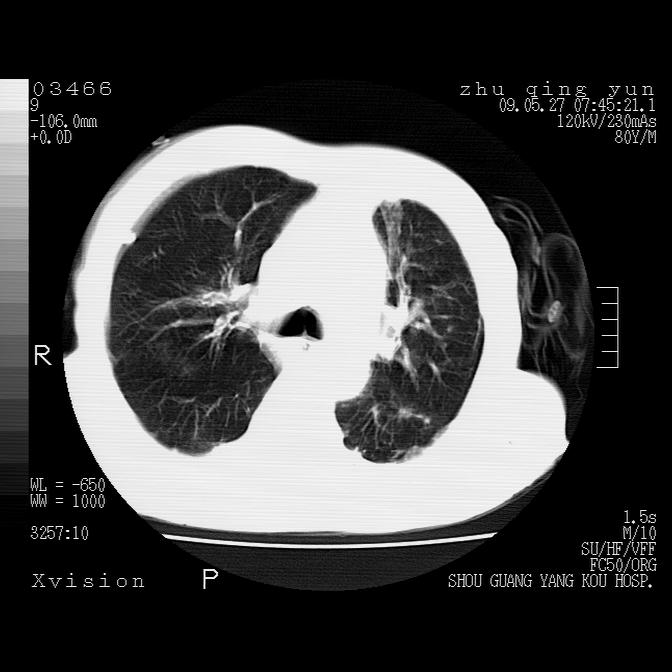

病人男性,年龄80,气喘来院,其他病史不太详细,1月前有过恶心,呕吐,在当地人民医院做过钡餐,诊断胃炎,

1)考虑左肺中央型肺癌并阻塞性肺炎,后下纵隔受侵伴纵隔淋巴结转移。2)双侧少量胸腔积液,胸膜增厚。3)心包积液。

左肺下叶见多发片状及结节状病灶,左肺基底段支气管闭塞,纵隔内见多发淋巴结肿大,纵隔向左侧移位,左侧胸廓变小。应该是左肺下叶中心型肺癌,纵隔淋巴结转移,左侧肺内转移,左肺基底段肺不张,阻塞性肺炎。

1)考虑左肺中央型肺癌并左肺下叶阻塞性肺炎、不张;左胸膜腔积液、心包积液、纵隔淋巴结转移;癌肿累及左心房。2)左心室大。冠状动脉壁钙化斑。

支持以上,左肺肿块应该是周围型吧,考虑左下肺周围型肺癌伴肺内转移,阻塞性肺炎,纵隔淋巴转移,左侧胸膜及心包转移